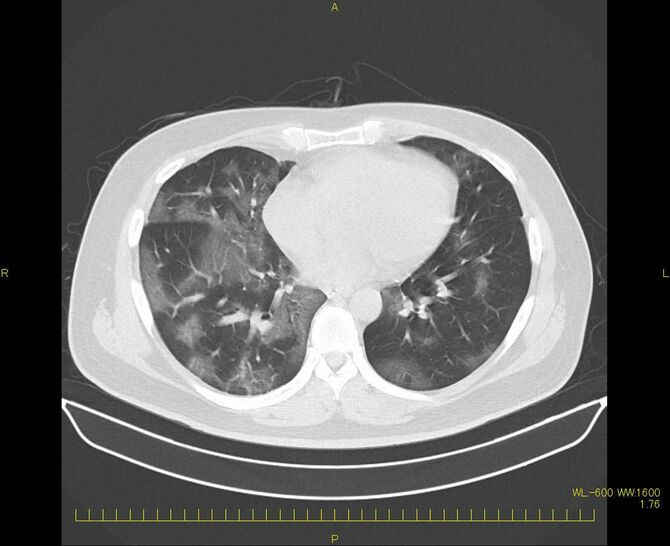

生死の境をさまよった当時の肺CT画像には、新型コロナの肺炎に特徴的な、「すりガラス状」の白い膜のようなものが写っている。